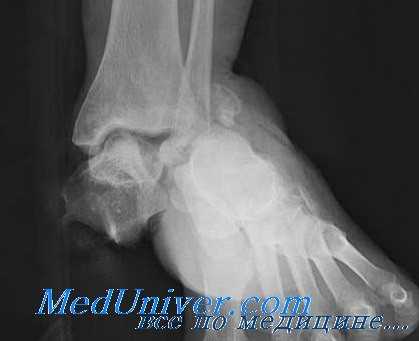

(Справа) У этого же пациента при рентгенографии голеностопного сустава в боковой проекции визуализируется вывих заднего и среднего отделов подтаранного сустава. Кроме того, выявляются переломы «задней лодыжки» и задней части тела таранной кости. Шейка таранной кости не повреждена. Наблюдается вывих таранно-ладьевидного сустава. (Слева) При рентгенографии голеностопного сустава в передне-задней проекции определяется вывих таранной кости. Ее головка ротирована латерально. Также выявляется перелом медиальной лодыжки.

(Справа) У этого же пациента при рентгенографии голеностопного сустава в боковой проекции визуализируется вывих таранной кости относительно всех суставных поверхностей. Перелом таранной кости отсутствует. В некоторых случаях таранная кость вывихивается наружу, повреждая кожные покровы.